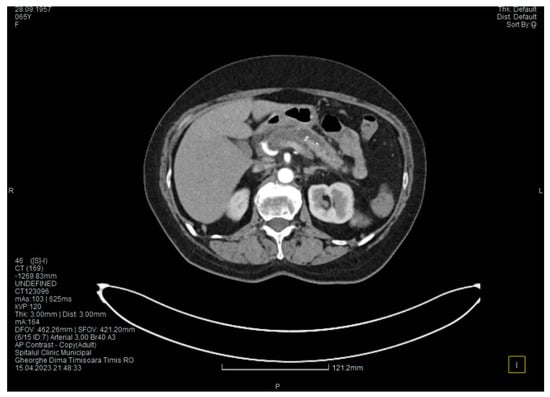

Laboratory tests showed a serum lipase level more than 10 times above the upper normal range. The contrast-enhanced computed tomography (CT) showed multiple calcifications in the pancreatic tissue, dilatation of the main pancreatic duct measuring approximately 12.5 mm (Figure 1), a non-iodophilic intraparenchymal cyst in the head of the pancreas measuring 23/25 mm, which was associated with acute inflammation (Figure 2), and densification of the peripancreatic fat, which was more intense at the head of the pancreas. In addition, enlarged pericephalic and periaortocaval lymph nodes were observed. There were no changes in the liver or the gallbladder, only a mild ectasia of the intrahepatic bile ducts, and no dilatation of the common bile duct. Other changes included multiple atheromas of the abdominal aorta. The symptoms, the lab results, and the CT findings led to the diagnosis of acute pancreatitis.

Figure 2. Initial CT scan shows a cyst in the pancreatic head.